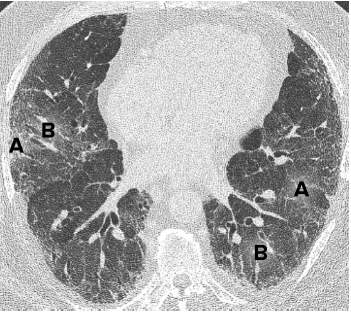

医学上将肺纤维化归属于弥慢性肺间质疾病,我们统称为肺间质疾病。近年来也被称为弥漫性实质性肺疾病,英文缩写为DPLD。这是呼吸系统非常复杂、病情多样的一类疑难病,它可细分为200多种不同类型,病因多样、病情发展不一。既有病情迅速进展、在几个月甚至几周内威胁生命的急进型,也有发展缓慢、逐渐蚕食肺间质的慢龟型,更有病情发展到一定阶段就平静的安稳型。它们的共同特点是造成了肺间质的损伤,但它们在病因、病理、发展过程、对治疗的敏感度和危害上差异很大,不能一概而论。医生只有通过多种检查,结合临床表现,才能明确间质性肺疾病的类型可能是由什么原因引起的。明确了诊断,才能帮助患者进行合理的治疗。